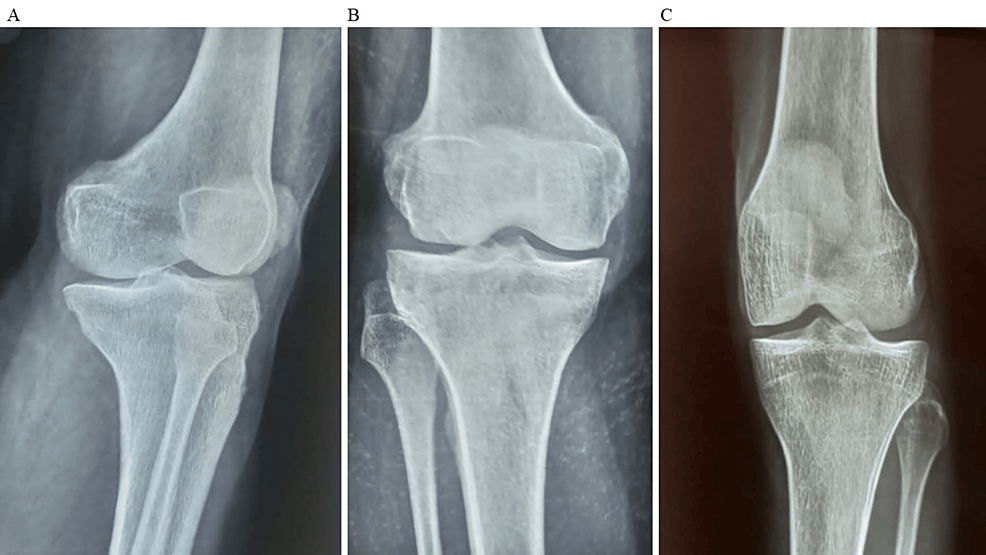

平均WOMAC評(píng)分從基線時(shí)的56.8±11.5下降到六個(gè)月時(shí)的41.2±10.6。此外,還監(jiān)測(cè)了不良事件的發(fā)生情況,報(bào)告了七起不良事件,占參與者的28.0%。這些發(fā)現(xiàn)強(qiáng)調(diào)了該治療在六個(gè)月內(nèi)減輕疼痛和改善功能結(jié)果方面的有效性。下圖2顯示了開(kāi)始干細(xì)胞治療后骨骼的側(cè)視圖和前后視圖。?